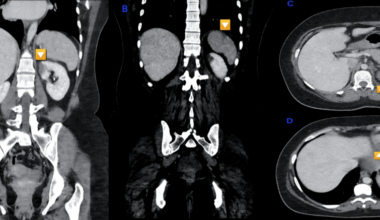

Renal and Splenic Infarctions: Unmasking Rheumatic Mitral Valve Disease in a Young Adult

• April 16, 2026